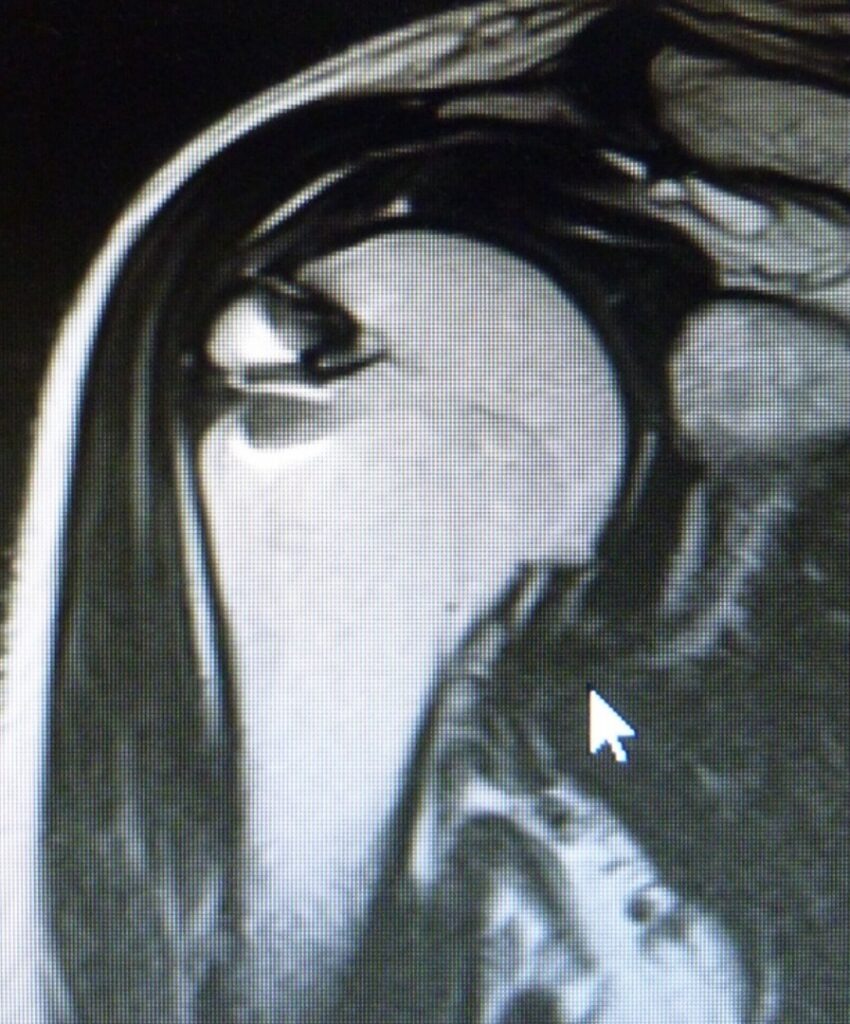

肩の関節は、球形の上腕骨頭と受け皿である肩甲骨関節窩との関係で成り立っています。

求心位 = 肩甲骨関節窩に上腕骨頭がうまく入った状態

求心位を保つためには、腱板や関節唇などいろいろな要素が影響しています。

求心位がくずれる原因は、腱板や関節唇の損傷、拘縮です。